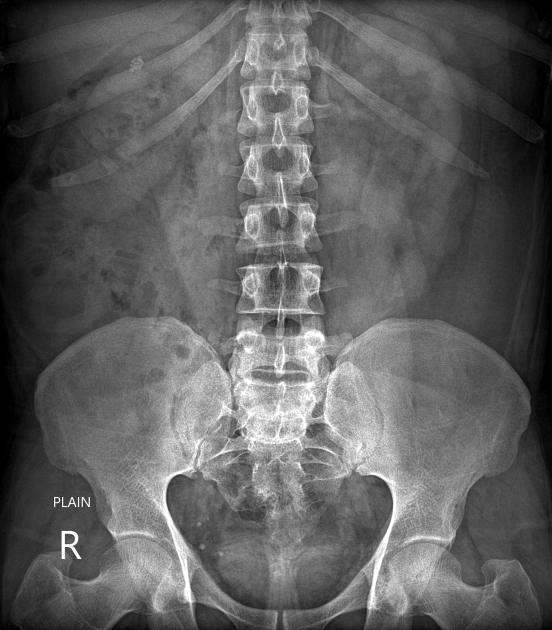

Thận xoay bất toàn (Abnormal renal rotation)